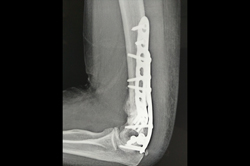

Elbow